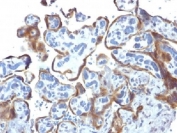

IHC staining of FFPE human bladder carcinoma tissue with TIMP2 antibody (clone TIMP2/8193R). HIER: boil tissue sections in pH 9 10mM Tris with 1mM EDTA for 20 min and allow to cool before testing.